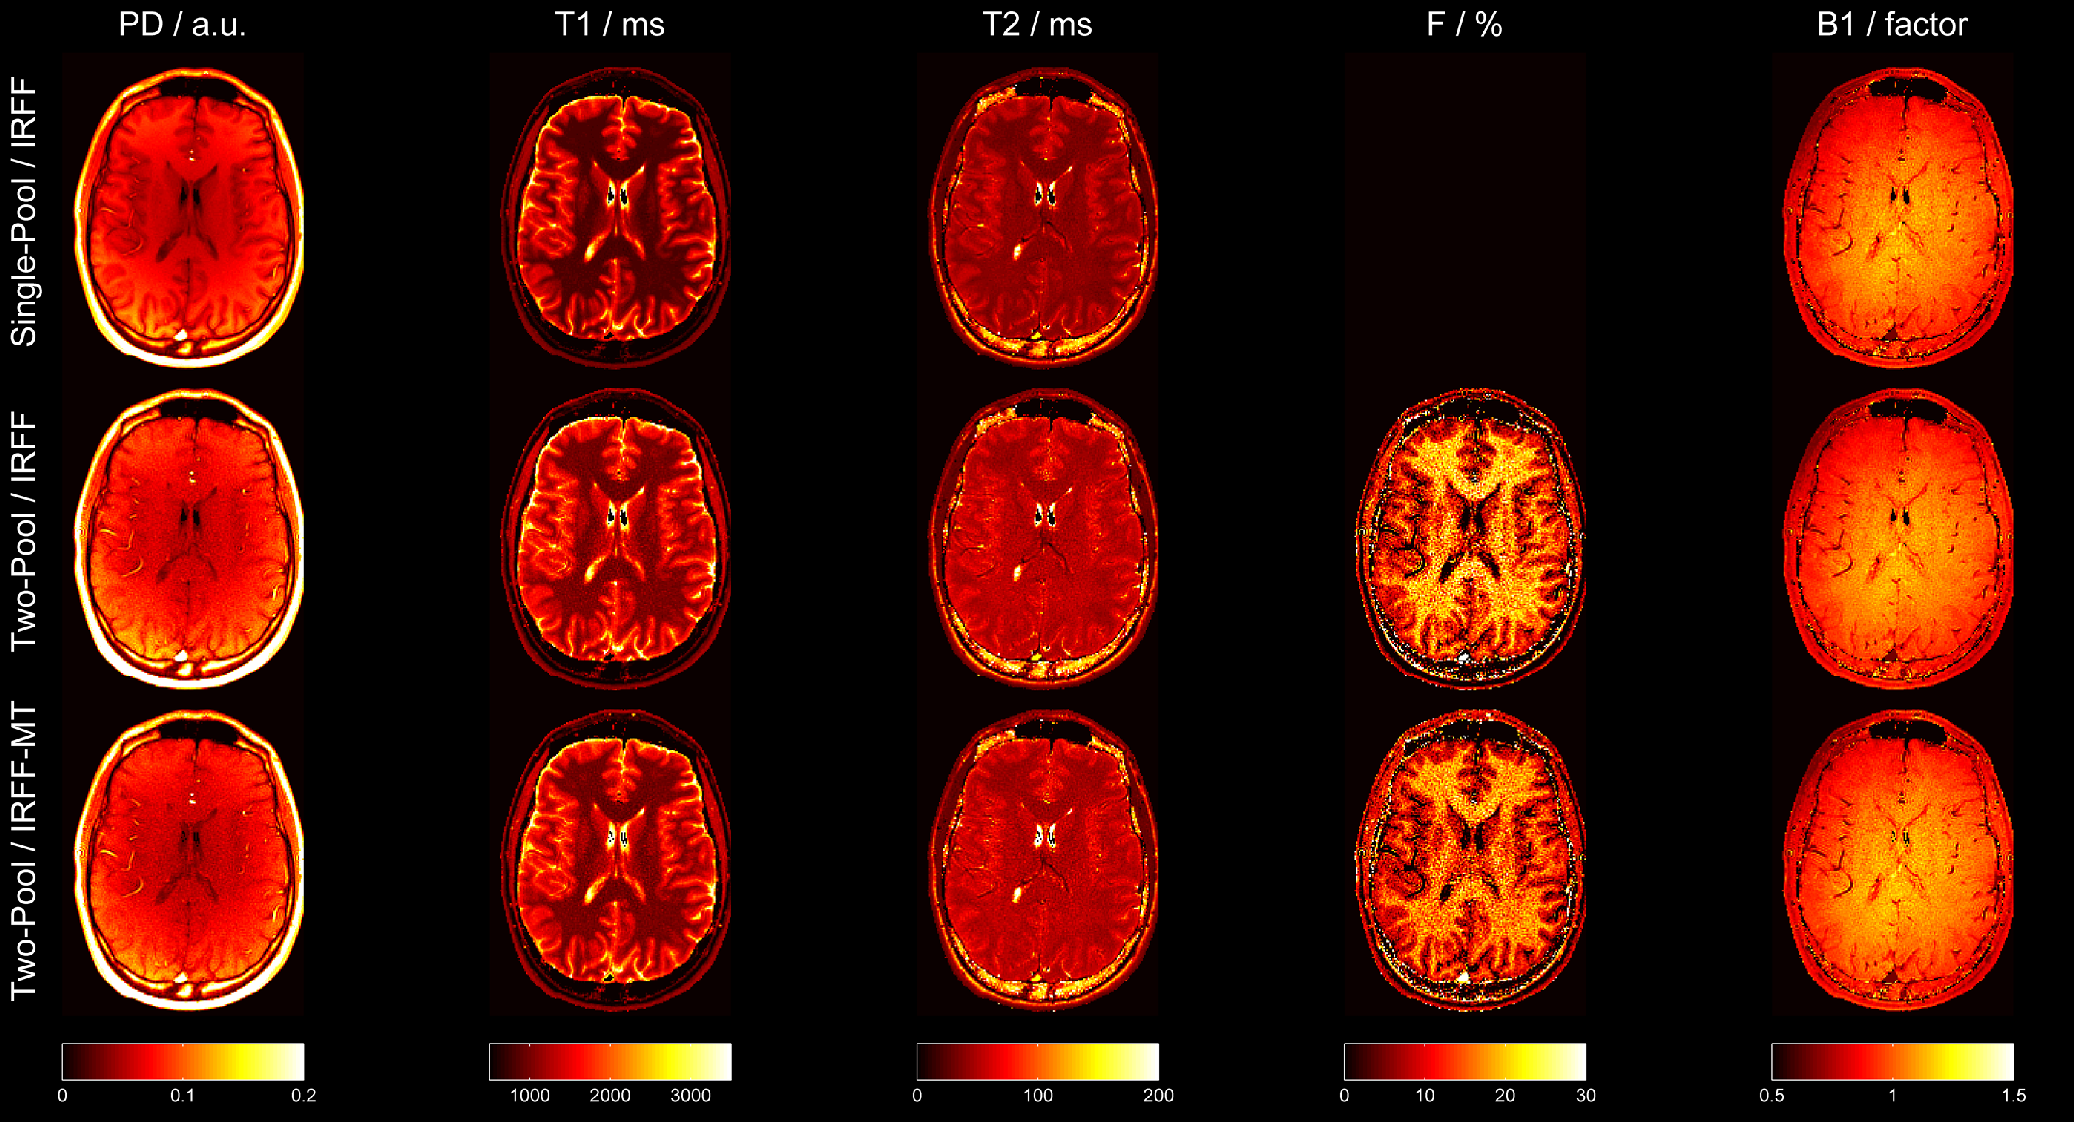

Example quantitative maps obtained from one volunteer using the three different dictionaries are shown in Figure 5. Regardless of the applied dictionary, all PD maps were affected by receive-field inhomogeneity and, unlike other parameter maps, should not be considered fully quantitative. Nevertheless, contrast between white and gray matter was observed in the PD maps reconstructed from the single-pool model, with lower PD in gray matter in comparison to white matter. Furthermore, in both T1subscript𝑇1T_{1} and T2subscript𝑇2T_{2} maps, lower relaxation values were observed when a single-pool model was used. Since this effect is stronger in white matter, the contrast between white and gray matter was reduced when using a two-pool model. Of note, the increase in T1subscript𝑇1T_{1} and T2subscript𝑇2T_{2} when accounting for MT was observed in vitro as well (see Figure 4a-b). The fractional pool size of the semi-solid pool (F) corresponds to a contrast that resembles MT maps in literature[20, 24, 25] with the highest fractional pool size in white matter, lower fractional pool size in gray matter, and no MT effect in CSF. When comparing IRFF versus IRFF-MT for the two-pool model, the latter, which employs MT pulses, resulted in lower fractional pool size. This may be linked to an overestimation of F𝐹F if MT effects are not sufficiently encoded in the IRFF fingerprint, as also demonstrated in vitro (see Figure 4b-c). The obtained B1+superscriptsubscript𝐵1B_{1}^{+} maps showed high flip angles in the center of the FOV with a smooth transition to lower flip angles in the periphery of the FOV. The B1+limit-fromsubscript𝐵1B_{1}+ field maps obtained from the different dictionaries appeared similar.

Refer to caption

Figure 5: Example quantitative maps obtained from one volunteer using a single-pool model (top), a two-pool model (middle) or a two-pool model with MT pulses in the sequence (IRFF-MT, bottom).